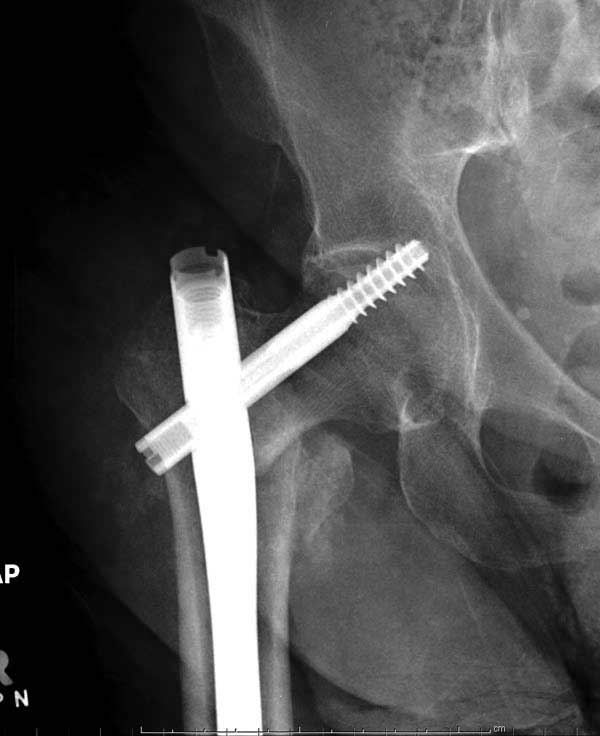

Такие “чужие осложнения” встречаются у всех и представляю банальный случай, который шаг за шагом показано как перерос в более сложный процесс... Больная 70 лет, множественные ко-морбидности, чрезвертельный перелом первоначально фиксирован Гамма 3. Осложнение в течение 6 недель, ревизия тотальной артропластикой и во время установки ножки обнаружена трещина диафиза (17), из малого доступа фиксация алло-графтом.

Повторно поступает после двух с половиной лет, где обнаруживается перелом на второй стороне. Немного сложно, но для фиксации выбрали Antegrade InterTan Smith Nephew Nail и с момента фиксации более 3х мес.

Имя     : 25 IT fx Rt  periprosthetic fixation CRM 3.JPG

Тип     : image/jpg

Размер  : 27484 байтов

Описание: отсутствует

Url     : http://weborto.net:8080/pipermail/ortho/attachments/20120510/52aada75/attachment-0047.jpg